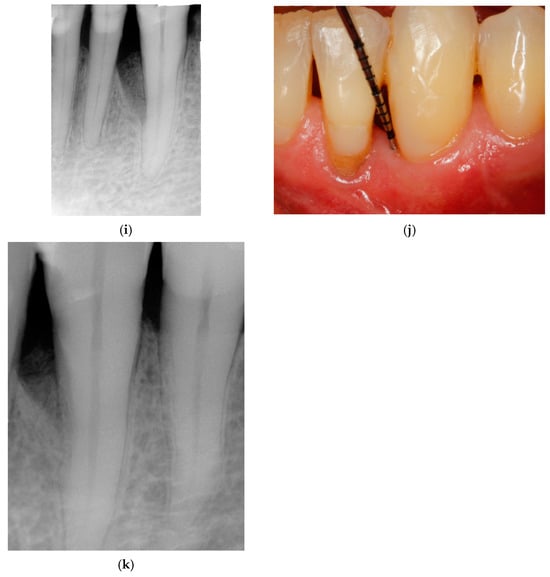

Entire Papilla Preservation Technique with Enamel Matrix Proteins and Allogenic Bone Substitutes for the Treatment of Isolated Intrabony Defects: A 3-Year Follow-Up of a Prospective Case Series

- Górski, B.; Kowalski, J.; Wyrębek, B. Entire Papilla Preservation Technique with Enamel Matrix Proteins and Allogenic Bone Substitute for the Treatment of Isolated Intrabony Defects: A Prospective Case Series. Int. J. Periodontics Restor. Dent. 2023, 43, 387–397. [Google Scholar]